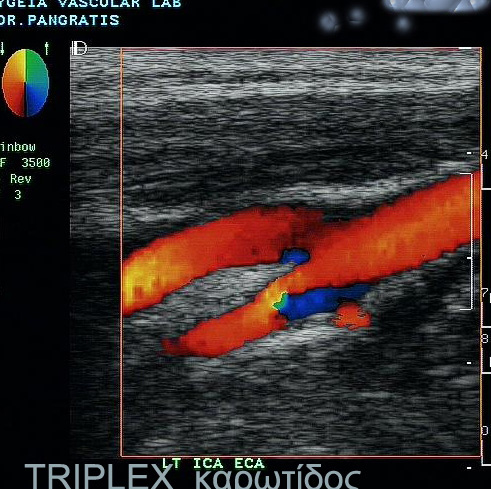

TRIPLEX ΓΓΓΓΓΓΓΓΓ ΓΓΓ ΓΓΓΓΓΓΓΓΓΓΓ ΓΓΓΓΓΓΓΓ

Γ ΓΓ ΓΓΓΓ ΓΓΓΓΓΓΓΓΓ ΓΓΓΓΓΓΓ, ΓΓΓΓΓΓΓΓΓ ΓΓΓ ΓΓΓΓΓΓΓΓΓ ΓΓΓ ΓΓΓΓΓΓΓΓΓΓΓ ΓΓΓΓΓΓΓΓ ΓΓ ΓΓΓ ΓΓΓΓΓΓ